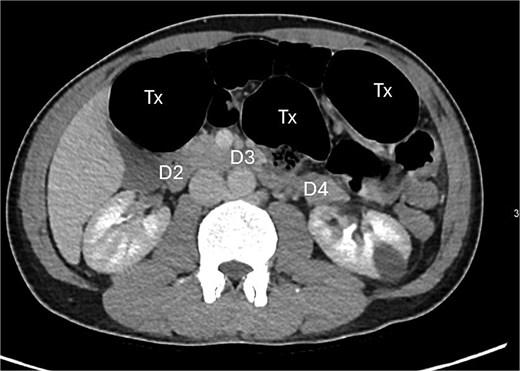

A contrast-enhanced computed tomography (CT) scan of the abdomen and pelvis demonstrated a large bowel obstruction with a transition point at the distal transverse colon with swirling of the mesentery. Downstream large bowel was collapsed. Upstream dilatation included the terminal ileum suggested an incompetent ileo-caecal valve. The gastric antrum was also involved in the internal hernia, resulting in gastric outlet obstruction. See Figs 1–5.

Axial CT image demonstrating distended transverse colon (Tx) and stomach (st).

Axial CT image displaying transverse colon in paraduodenal hernia (PDH) with resulting distension of transverse colon (Tx) and stomach (st).

Posterior displacement of the duodenum (D4) due to herniated transverse colon.